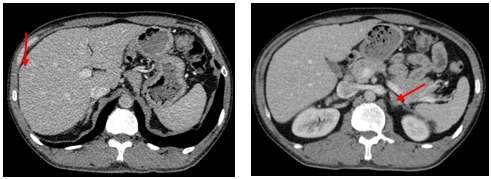

-         CT ổ bụng:

Hình 3. Trên phim chụp CT ổ bụng: Nhu mô gan sát bao gan phân thùy S5 có nốt giảm tỷ trọng trước tiêm, ngấm thuốc kém sau tiêm, đường kính 10mm – Theo dõi tổn thương thứ phát. Dày tuyến thượng thận trái.

Trên phim chụp cắt lớp vi tính ổ bụng:

Trước điều trị:

Sau 3 tháng điều trị: Tổn thương gan và thượng thận đã biến mất.

Hiện tại trong quá trình theo dõi gan và thượng thận 2 bên vẫn chưa xuất hiện tổn thương mới.